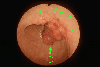

Type 1 (protuberant type) advanced gastric cancer with a superficial elevated type (IIa) at the margin of the lesion.

Tokyo Pref., Cooperative study between National Cancer Center and Kyushu Cancer Center

Malignant epithelial tumor/Adenocarcinoma